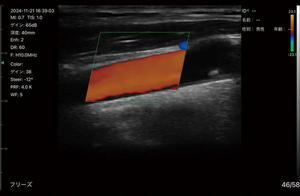

コンベックスとリニアプローブを一体化したデュアルプローブと,血流を視覚的に表示するドプラ機能の搭載により,1台で幅広い領域/部位へ使用可能。

カラードプラ使用イメージ(頸動脈)